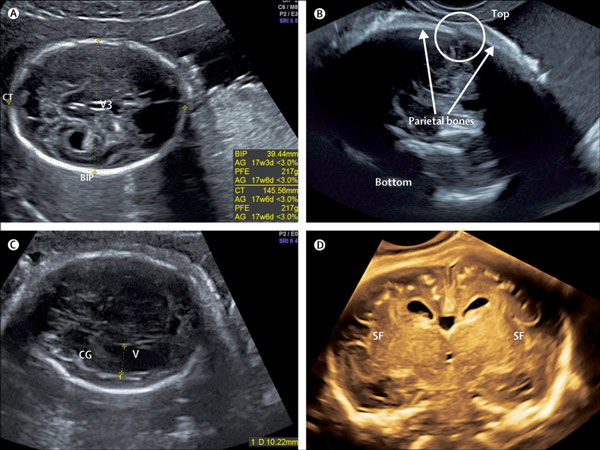

سونوگرافی سر و مغز کودک شما را بررسی می کند. شرایط مغزی، اگرچه نادر است، اما در این مرحله قابل مشاهده خواهد بود.

صورت نوزاد بررسی می شود و در این هنگام شکاف لب یا کام تشخیص داده می شود.

ستون فقرات نوزاد بررسی می شود تا بررسی شود که آیا استخوان ها به درستی شکل می گیرند و پوست کودک ستون فقرات را می پوشاند.

دیواره شکم نوزاد در مرحله بعدی قرار دارد. سونوگرافیک بررسی می کند که آیا تمام اندام های داخلی پوشیده شده اند یا خیر.

سونوگرافی قلب نوزاد، به ویژه رگها و شریانهای اصلی را بررسی میکند تا مطمئن شود که آنها خون را به قلب کودک شما منتقل میکنند.

معده نوزاد نیز مورد بررسی قرار می گیرد، جایی که مایع آمنیوتیکی که کودک شما در آن خوابیده است را می بینید. معمولاً شبیه یک حباب سیاه است.

کلیه های نوزاد در مرحله بعدی معاینه می شوند و سونوگرافیک بررسی می کند که آیا کودک شما دو کلیه دارد یا خیر.

سایر قسمت های بدن کودک شما مانند بازوها، دست ها، پاها و سایر قسمت های بدن برای بررسی کامل بودن آنها.

جفت و بند ناف نیز بررسی می شود، در صورتی که ممکن است در قرار دادن بند ناف کودک شما مشکلی وجود داشته باشد.